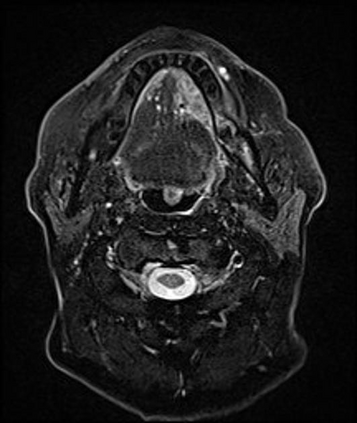

In this study, we aim to initiate the development of Radiology Foundation Model, termed as RadFM.We consider the construction of foundational models from the perspectives of data, model design, and evaluation thoroughly. Our contribution can be concluded as follows: (i), we construct a large-scale Medical Multi-modal Dataset, MedMD, consisting of 16M 2D and 3D medical scans. To the best of our knowledge, this is the first multi-modal dataset containing 3D medical scans. (ii), We propose an architecture that enables visually conditioned generative pre-training, allowing for the integration of text input interleaved with 2D or 3D medical scans to generate response for diverse radiologic tasks. The model was initially pre-trained on MedMD and subsequently domain-specific fine-tuned on RadMD, a radiologic cleaned version of MedMD, containing 3M radiologic visual-language pairs. (iii), we propose a new evaluation benchmark that comprises five tasks, aiming to comprehensively assess the capability of foundation models in handling practical clinical problems. Our experimental results confirm that RadFM significantly outperforms existing multi-modal foundation models. The codes, data, and model checkpoint will all be made publicly available to promote further research and development in the field.